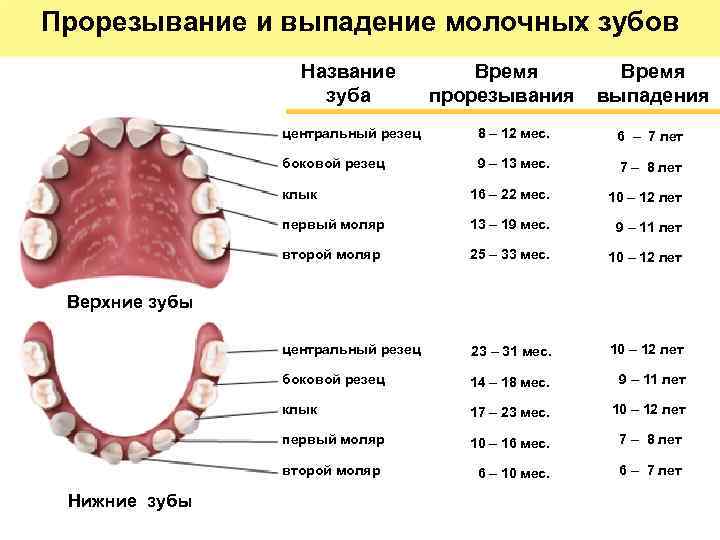

Приблизительная очередность выпадения и смены зубов:

Возраст ребенка Зубы

6 – 7 лет – Нижние, а за потом верхние центральные резцы, первые моляры

7 – 8 лет – Боковые резцы

9 – 10 лет – Первые премоляры

10 -11 лет – Прорезывание клыков, вторых премоляров

11 -13 лет – Вторые моляры

Когда выпадают молочные зубы у детей —схема

Когда выпадают молочные зубы у детей —схема

Молочные зубы у детей: схема выпадения

Выпадение начинается с резцов и далее в том же порядке, что и их прорезывание. В норме выпадать зубки у ребенка должны согласно следующему графику:

- Центральные резцы выпадают к 6-7 годам.

- Вторые резцы начинают выпадать к 7-8 годам.

- Первые моляры выпадают к 10 годам.

- Клыки и вторые моляры к 12 годам также заменяются на постоянные.

Стоит помнить, что возраст указан условно. Если сказано, что начинается выпадение в 6 лет, то смена может происходить в пять лет или в семь. Кроме того, коренные зубы у ребенка растут на свободном месте, поэтому появляются раньше, чем начинают выпадать молочные. Впервые прорезываются они иногда уже к пяти годам, но при этом они являются постоянными.